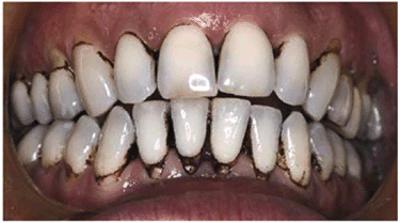

Figure 16-6: Black tobacco stain from dipping snuff for 15 years.